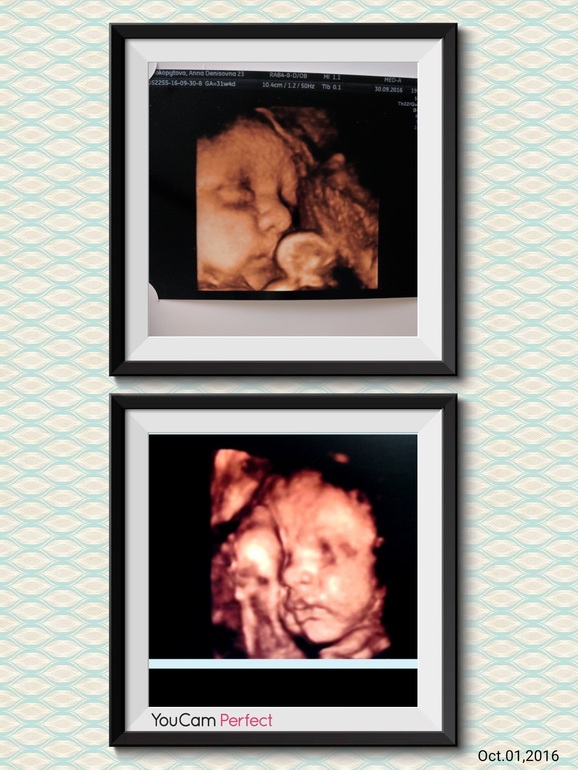

Наше 3 скрининг узи

Димасик наш лег правильно, головкой вниз.Все органы в порядке, развивается хорошо.Я яички наши уже сидят где нужно, мальчик совсем не стеснительный🤣Соответствует сроку,31+4, вес 1905.Есть несколько моментов которые огорчили.Первое это накинутся пуповина на шею, в петлю не замоталась, но как-то не нравится мне это… и опять голова большая(как и у первого сына, мы до сих пор головастики), а это значит, что в перспективе опять разрывы, эпизио, швы...😖Мало того что и так узко там все(несмотря на внушительные размеры моей опы,)так еще и зашили как девочку после первых родов)… Вот такие пироги.Моську сын показал, Сравнила фото с узи первого(к слову родился такой- же как на УЗИ в 31 неделю был) мама говорит похожи, а мне кажется что нет, есть конечно что-то схожее но не сильно.Как вы считаете?(сверху младший, снизу старший)И сколько ваши детишки весят на этом сроке?